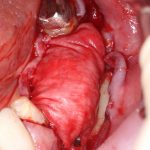

Вот клиническая картина через 4 месяца после ранее проведенной имплантации с остеопластикой:

Как видишь, коллеги из недалекой дружественной страны не осилили снятие швов. Мне это не нравится, хотя и объясняет, почему люди готовы ехать за тыщи километров ради 20-минутной операции удаления зуба мудрости.

Ну хорошо. Швы сняли. Делаем разрез. Обрати внимание, что после всех проведенных операций у нас остается очень небольшой по ширине слой жевательной слизистой оболочки: